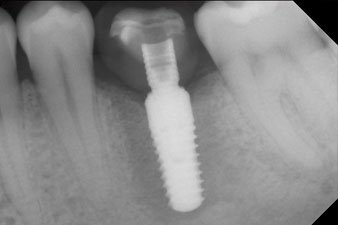

Implantat

Fig. 3: After preparation with the Implantmed implantology motor, an implant (diameter 4 mm, length 12 mm) was screwed in by the motor at a torque of 43 Ncm.

The implant was placed as planned after thorough removal of the granulation tissue (blueSky, bredent).

SmartPeg

Fig. 4: SmartPeg measuring posts screwed on to measure the implant stability quotients with the integrated W&H Osstell ISQ module.

The torque used for the machine-driven placement was 43 Ncm. In addition, after screwing a measuring post (SmartPeg) specially matched to the implant, the ISQ value was measured with the probe of the W&H Osstell ISQ module.

This module is an optional extra for the W&H Implantmed and is docked to the implantology motor (see Fig. 11). The dimensionless ISQ value immediately after insertion was 64 orovestibular and 68 mesiodistal (maximum value = 100).